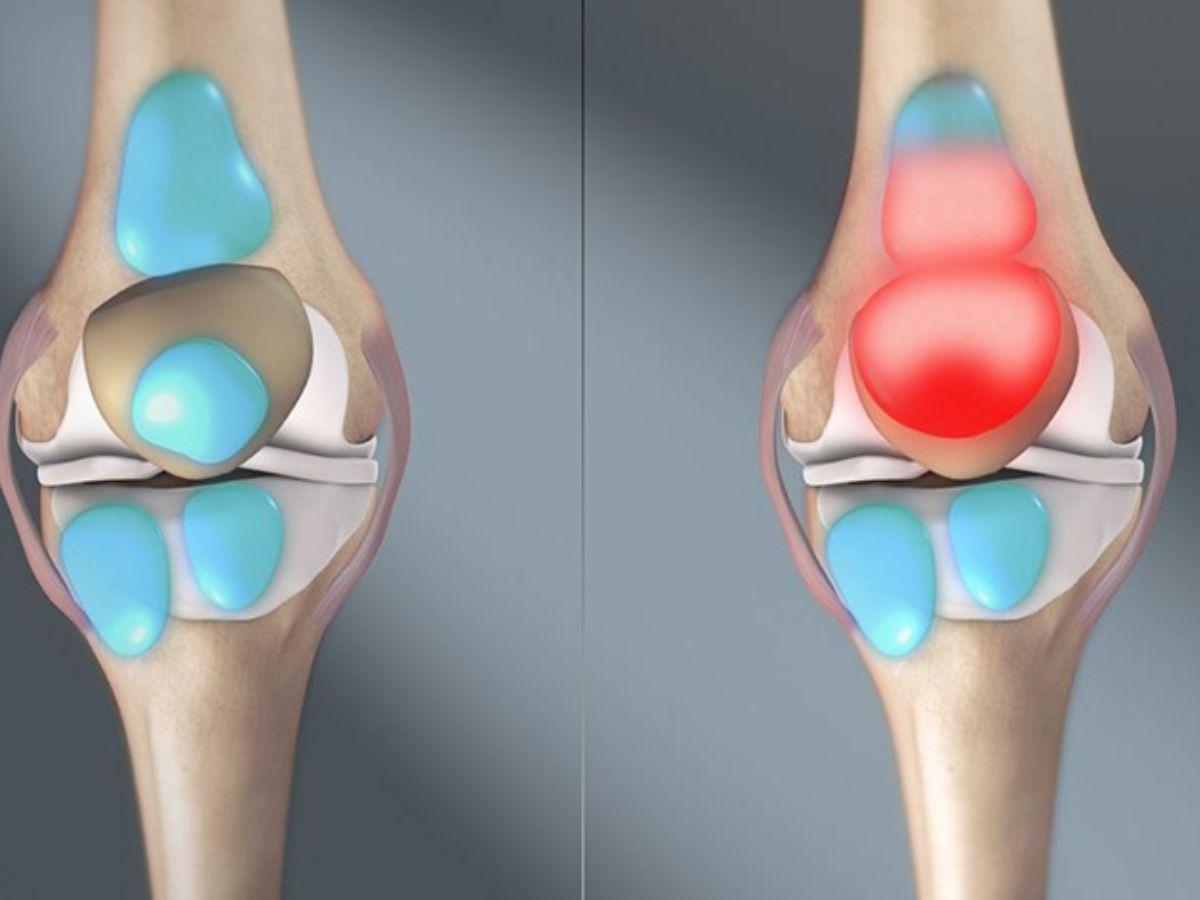

Viêm khớp gối

Viêm khớp gối là tình trạng viêm do chấn thương, bệnh lý tự miễn hoặc thoái hóa khớp gây ra. Tình trạng tổn thương này ảnh hưởng đến màng hoạt dịch, sụn và xương dưới sụn, gây đau nhức, sưng tấy và khóa cứng khớp khi đi bộ, làm suy giảm chức năng vận động và biến dạng khớp nghiêm trọng.

Viêm bao hoạt dịch

Viêm bao hoạt dịch là bệnh lý viêm của lớp bao khớp do chấn thương hoặc vận động quá sức trong thời gian dài và có khả năng tái phát nhiều lần sau khi điều trị. Dấu hiệu chính của tình trạng này là sưng tấy đỏ khớp gối, có cảm giác đau nhức và cứng khớp, có cảm giác ứ dịch, tràn dịch khớp gối và khó khăn khi di chuyển.